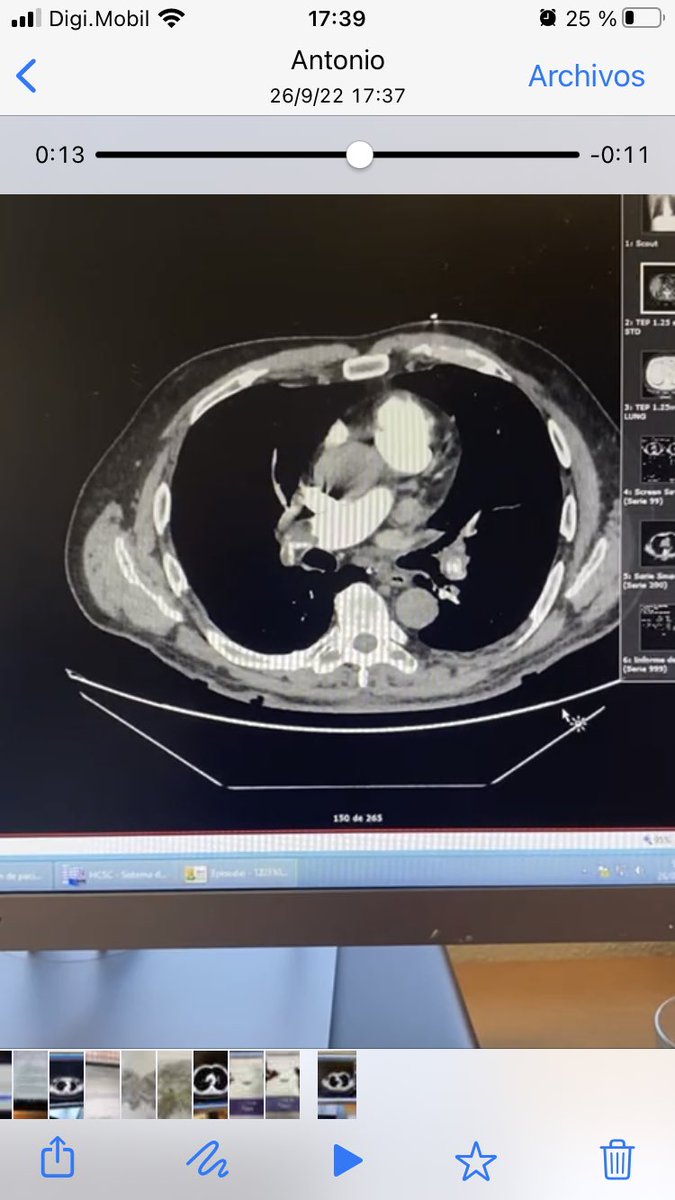

Yesterday we celebrated our 50th Acute PE Thrombectomy @Sta Cruz Hospital, Lisbon, with a quite impressive case in a young woman @InariMedical Flowtriever 24 Fr

7

26

149